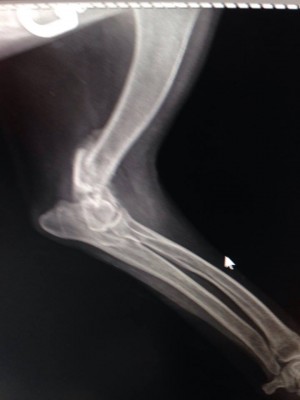

Надо мелкой рентген срочно делать

На лапу не наступает.... гипс не помню сколько был, но возможно, не правильно сложили

Вобщем все гораздо хуже оказалось.Только характер приятный,ласкавая.

Очень паршивый перелом.... сложная операция.

Не понятно куда и зачем одевали гипс.... зато стерилизовали.